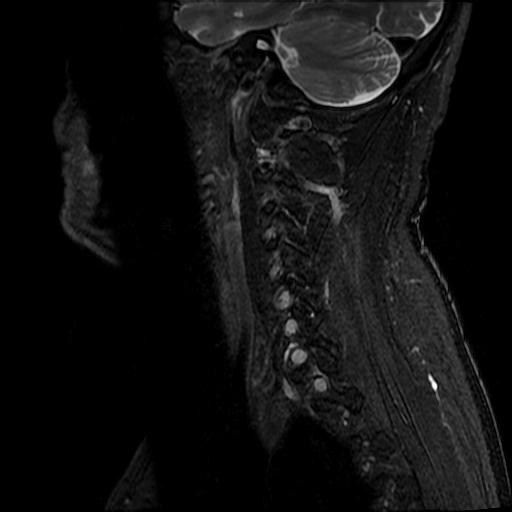

| Study | ID | Date | Accession # | Thumbnails | Report | XR ELBOW, AP & LAT, LEFT | 2766356 | 08/21/2019 | 2766356 | ... | MR WHOLE SPINE (FULL STUDY) | 32376 | 08/23/2019 | 2766095 | ... | XR CERVICAL SPINE, AP & LATERAL | 2765876 | 08/20/2019 | 2765876 |